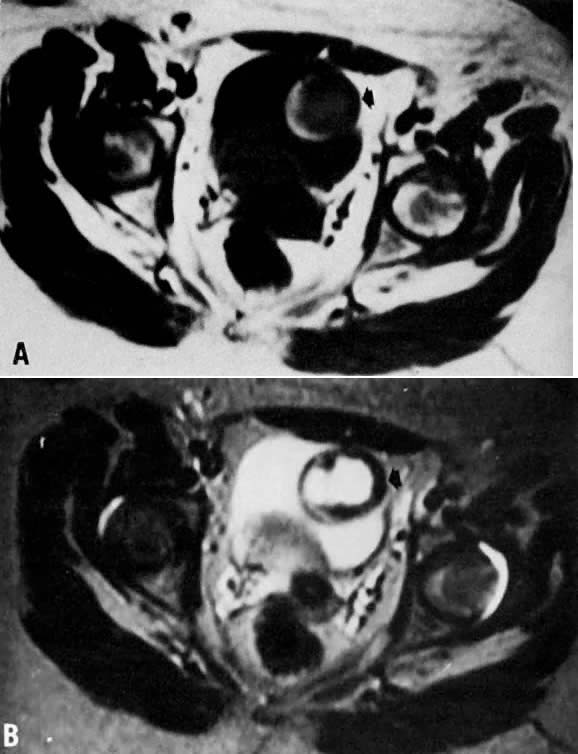

Fig. 9. A. Recurrent cervical carcinoma. Transverse T1-weighted image through the pelvis showing a large left pelvic soft-tissue mass ( arrows ). B. With T2 weighting, the mass in A now shows increased signal intensity consistent with recurrent carcinoma.